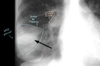

96

4 = trombo

97

TEP